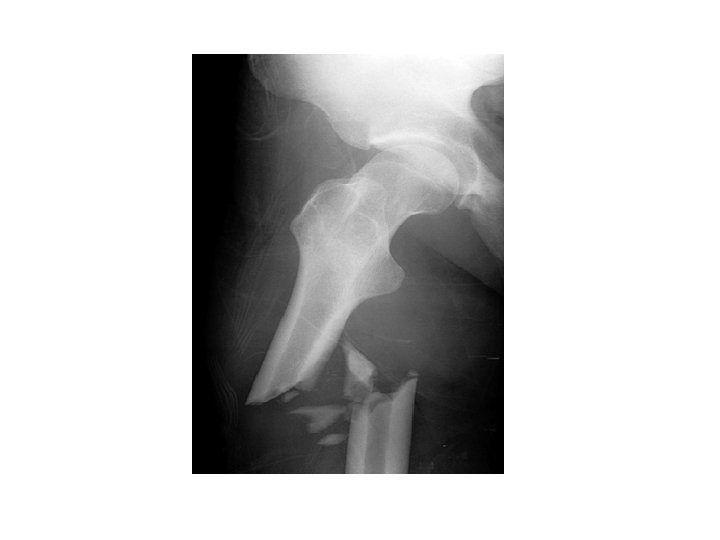

B. Fractures 1. Simple bone breaks cleanly, does not break through skin

B. Fractures 2. Compound broken ends protrude through the skin, risk of bone infection

B. Fractures 3. Greenstick Does not break completely Greenstick: (children)